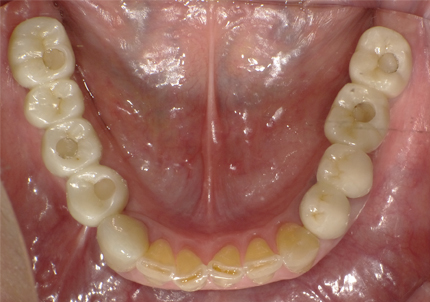

1.初診時口腔内(2007年6月30日)

↑ 2007年6月30日(初診)